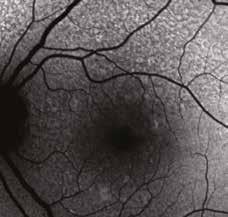

Nel corso del follow-up di tali pazienti si verificava spesso, come ben evidenziato dall’imaging in auto-fluorescenza (AF) nel tempo, un rapido e significativo incremento delle aree atrofiche, solo pochi mesi dopo la sostituzione del DHA algale dall’integratore Areds2 con olio di Krill, cosa mai avvenuta nel precedente lungo follow-up dei medesimi pazienti durante integrazione con DHA algale. (Fig. 2)

Fig. 2. Notare che nei 18 mesi di integrazione l’auto-fluorescenza della macula della paziente di 78 aa con AMD rimane libera da significative aree atrofiche, fintanto che il paziente continua ad assumere la formula antiox AREDS2 arricchita di olio algale, mentre solo 9 mesi dopo la sostituzione del DHA algale con DHA da pesce Krill, si osserva la rapida comparsa di significative ed invalidanti aree atrofiche a coinvolgere diffusamente l‘area maculare,altamente impattanti sull’acuità visiva della paziente fino a rendere estremamente difficoltosa la capacità di lettura, con un calo visivo fino a 2/10 da 8-9/10.